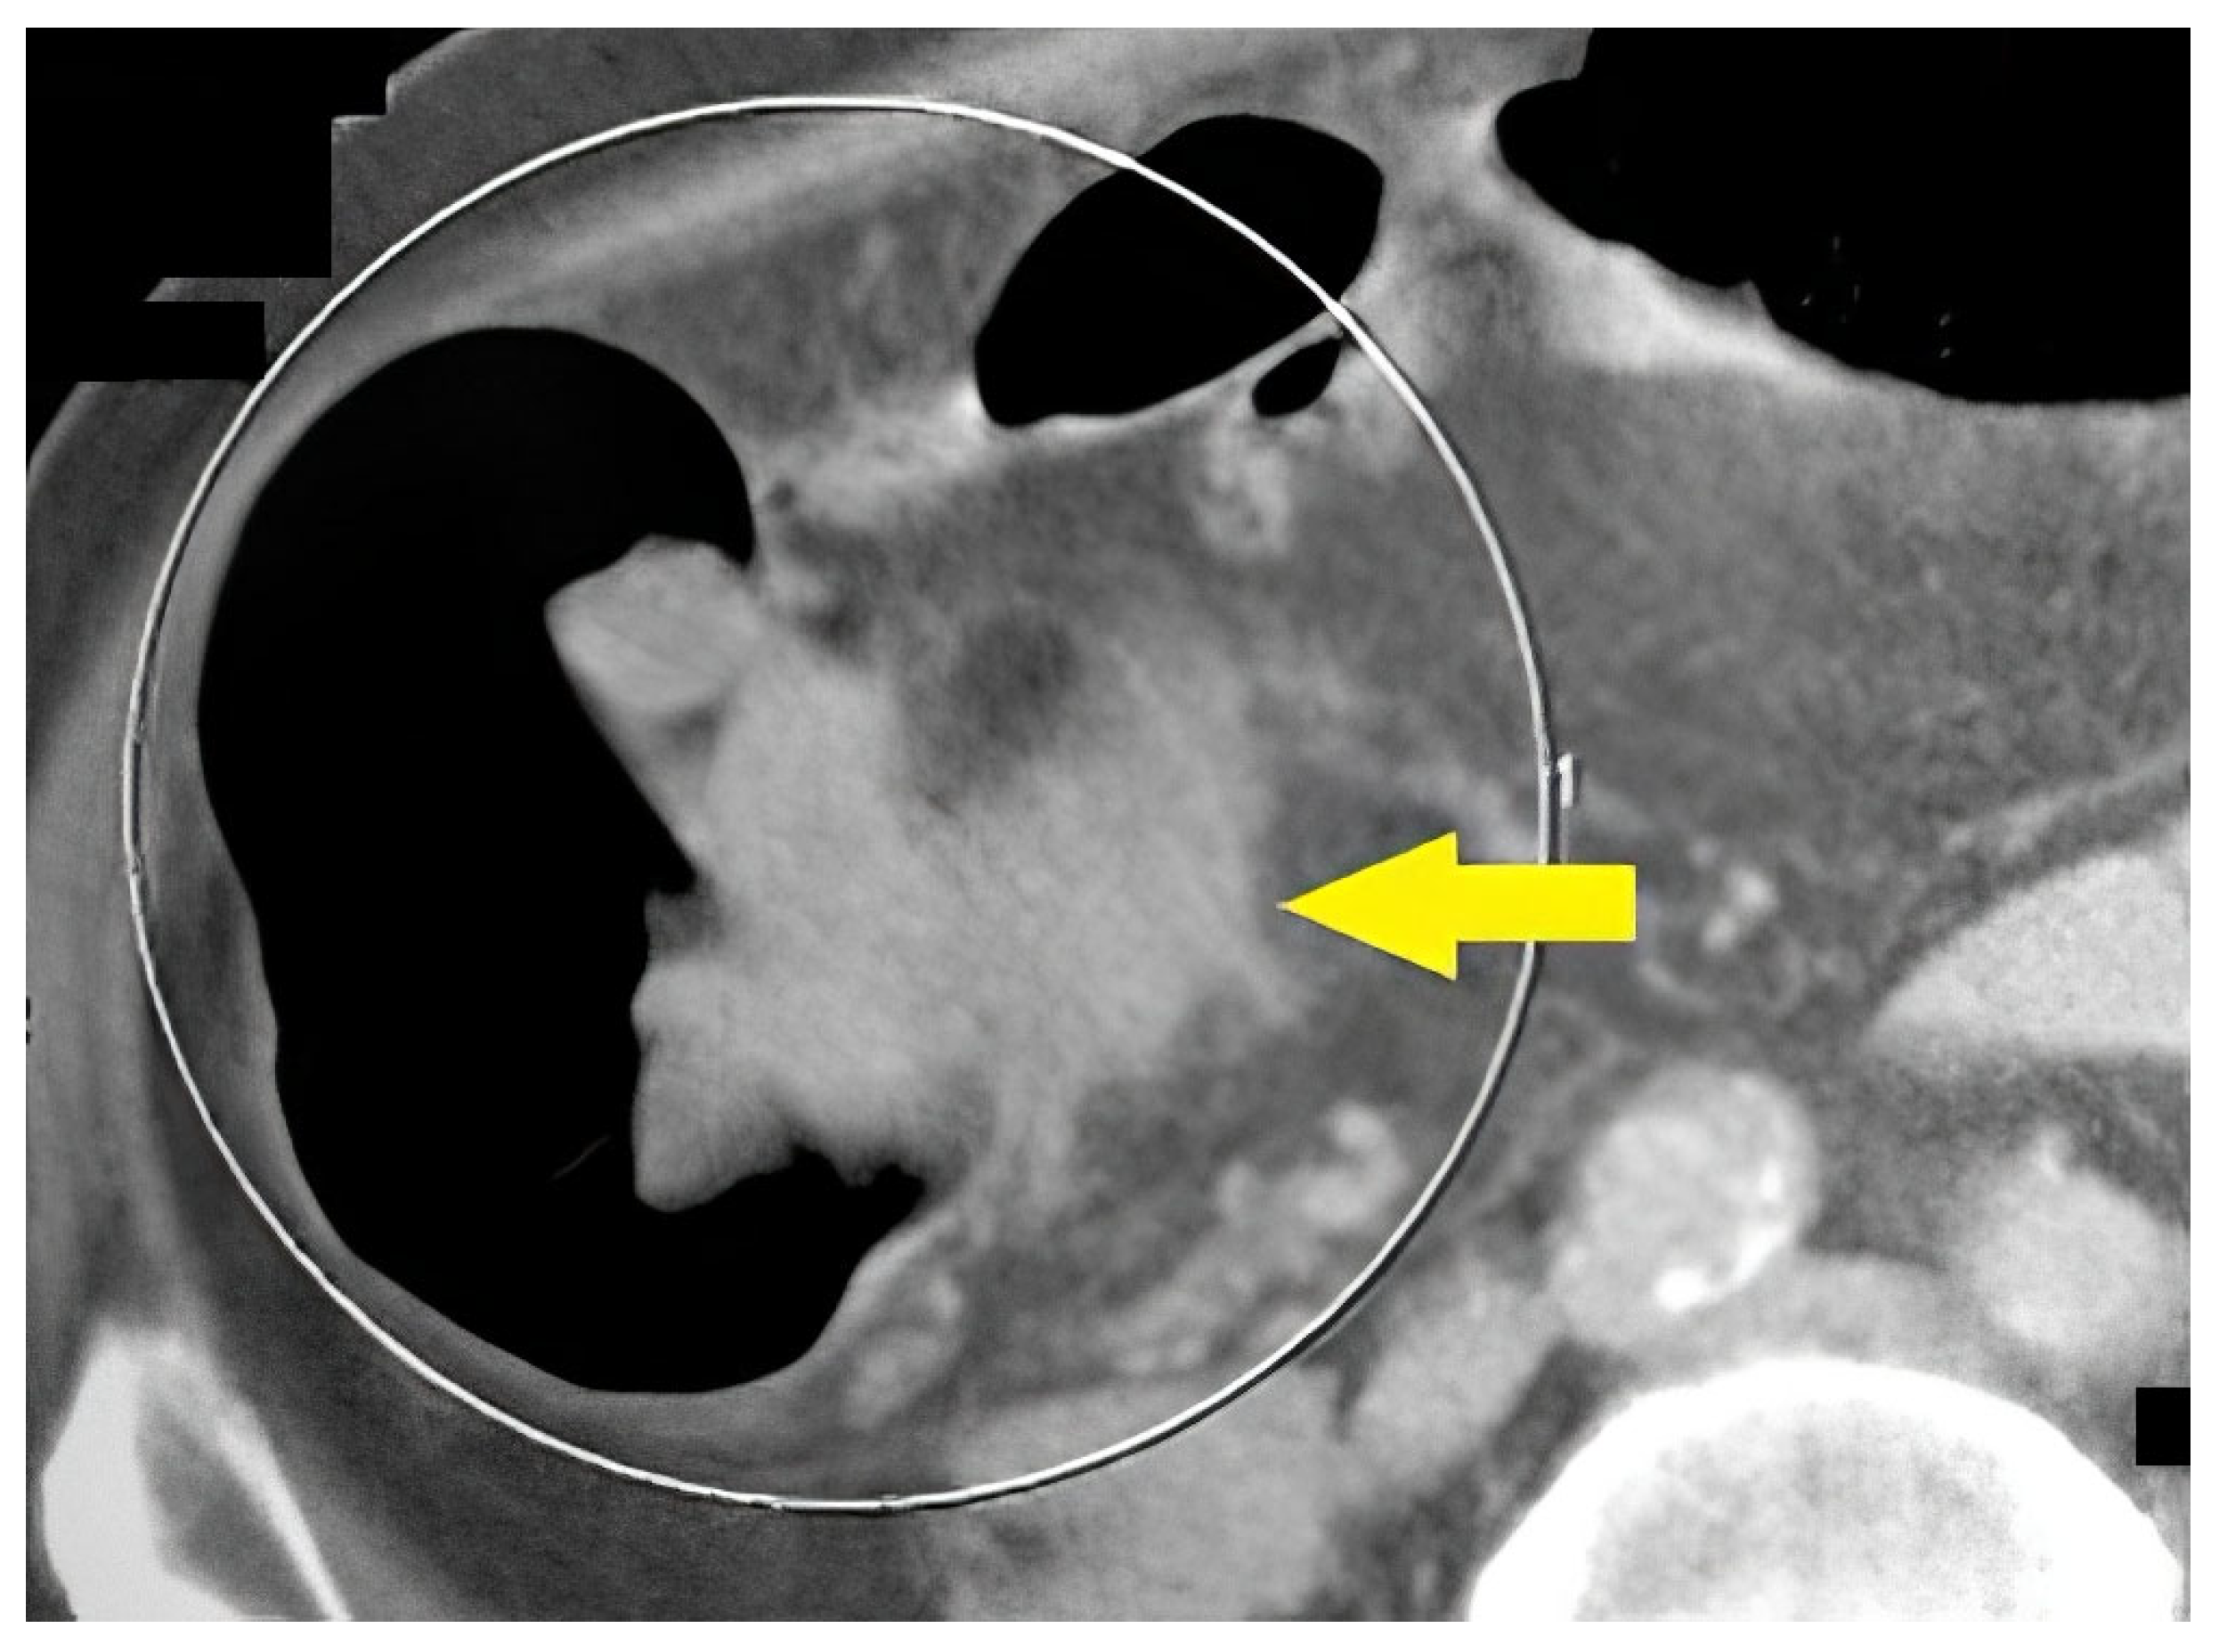

Life Free FullText High Concordance of CT Colonography and

Life Free FullText High Concordance of CT Colonography and How Do They Do A Ct Colonography Ct colonography offers important advantages over optical colonoscopy. Ct colonography is a way of looking inside your bowel and abdomen. Ct (computed tomography) colonography is a test that uses ct scans to check the large bowel (colon) and back passage (rectum). This information explains how it is done, what to expect, and the. As with stool testing, ct colonography has. How Do They Do A Ct Colonography.